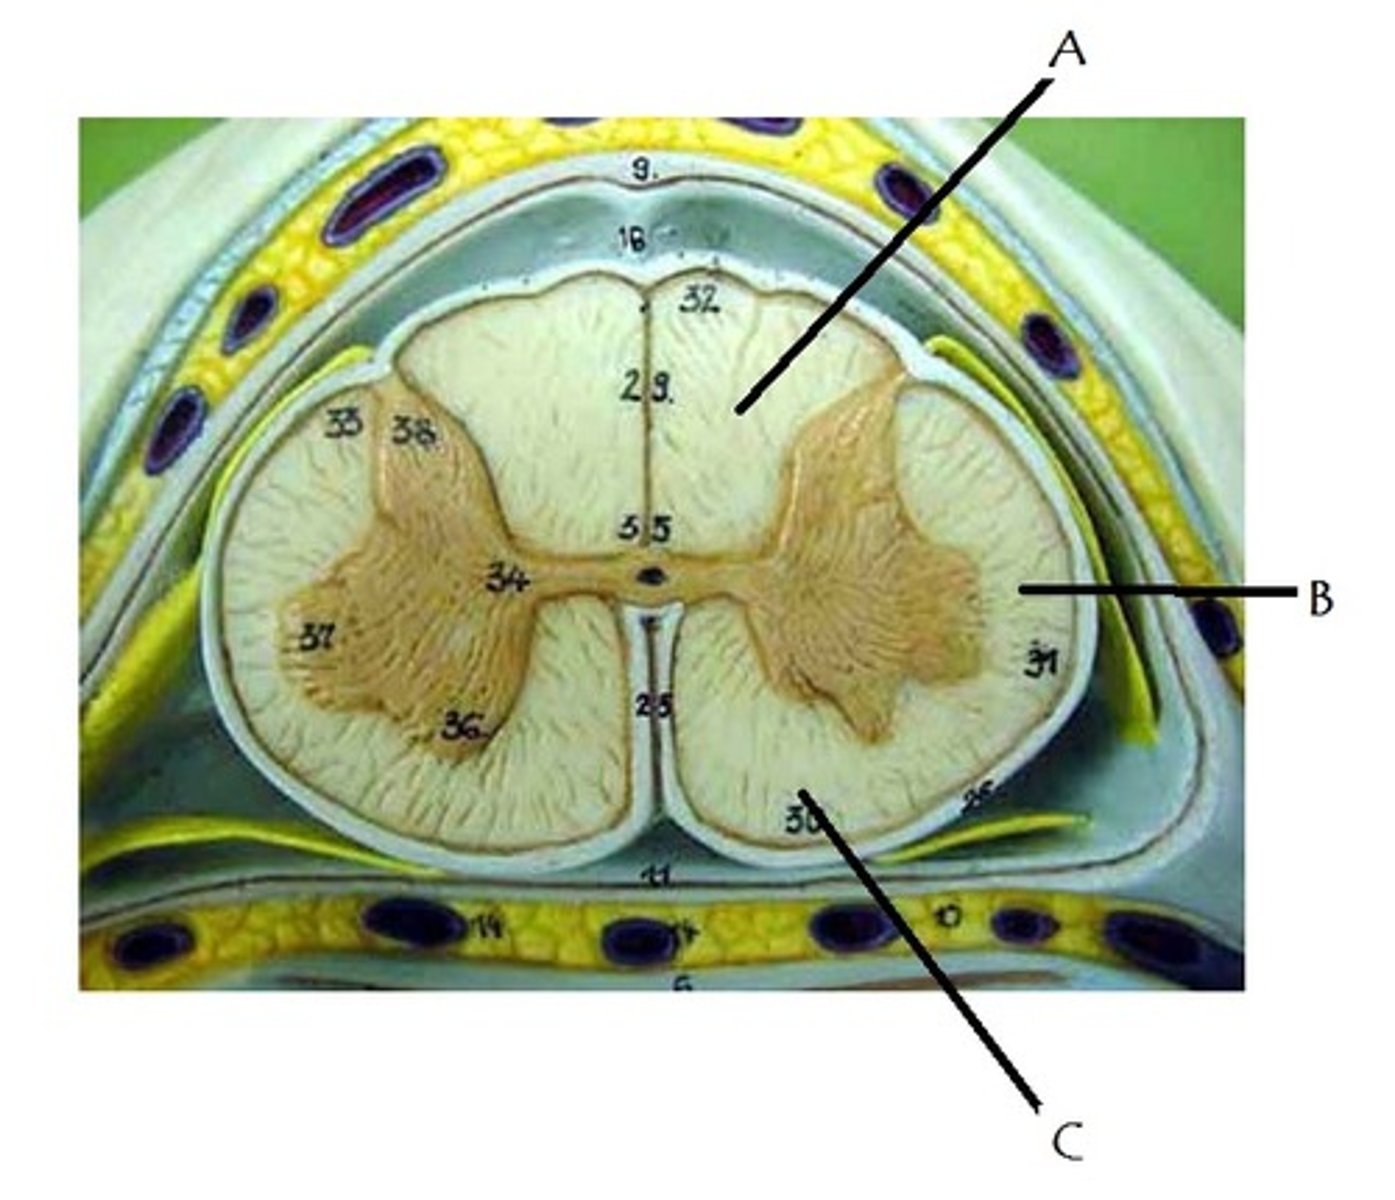

posterior median sulcus

anterior median fissure

posterior white column

A

anterior white column

C

lateral white column

B

posterior gray horn

anterior gray horn

lateral gray horn

gray commissure

Part of grey matter connecting the two halves of the grey matter in spinal cord

central canal

Hole in the center

Name this passageway

epidural space

dura mater

thick, outermost layer of the meninges surrounding and protecting the brain and spinal cord

subdural space

space between dura mater and arachnoid mater

arachnoid mater

middle layer of the meninges

B on model

subarachnoid space

a space in the meninges beneath the arachnoid membrane and above the pia mater that contains the cerebrospinal fluid

pia mater

the delicate innermost membrane enveloping the brain and spinal cord.

denticulate ligaments

extensions of pia mater that secure cord to dura mater laterally